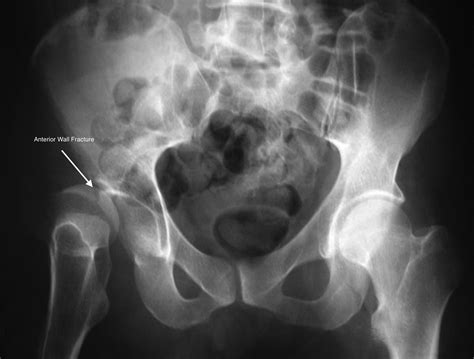

Anterior Column Involves the front part of the socket, often extending to the pelvic brim.

• Standard Radiographs: Pelvic AP and Judet views to assess the general orientation of the pelvis.

• CT Scans: The gold standard. A CT scan provides a detailed view of the articular surface and the displacement of fracture fragments.